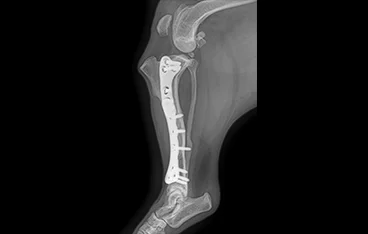

• 골반골절

• 골반골절 수술 전

골반골절 수술 후